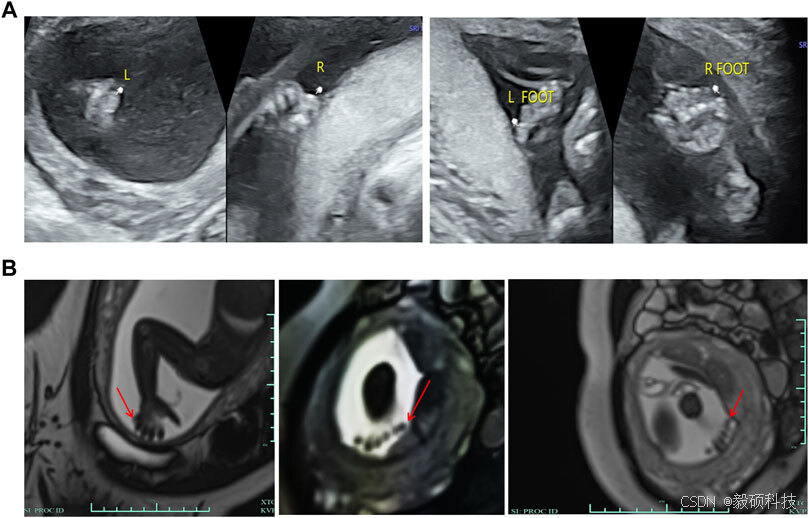

图3 胎儿的临床特征

(A) 超声显示双脚小趾外侧和双手小指外侧有第六趾的回声,大小约为0.6*0.4厘米,其中没有明显的骨骼结构。 (B) MRI显示右手小指外侧有指状信号阴影,而左手手指数量因胎儿位置不清晰。双脚均可见六个趾状信号阴影。